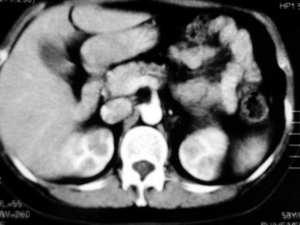

应该为脾脏来源的,囊性肿瘤,从前后ct片显示,有轻度强化改变(ct值),但好像有快速消退的感觉???

ct示脾内缘囊性低密度影,强化后其边缘实质部分与脾同步,且强化程度一样,

脾脏来源的,低密度,边界清,有分隔,有强化。

左侧肾上腺受压,病变不是来源于肾上腺,mri脂肪抑制病变为高信号,除外脂肪瘤,考虑来源于脾脏可能性大,强化后壁与脾脏强化基本相似,其内见分隔,囊腺瘤,血管瘤不除外。

cor上显示病灶与肾上腺无关,stir仍呈高信号,增强ct扫描各期均为低密度,且感觉张力较高,还是符合脾脏囊肿性病变的表现。

首先病灶的部位位于脾脏,这一点应该可以达成共识,因为它相邻的实质部分与脾脏同期.同时强化,并可见“鸟嘴”征象。第2:囊性病灶没有明显强化,在延期扫描的时候也是一样。也无病灶缩小的特征。所以我感觉应该考虑:脾脏囊性占位(脾脏囊肿可能性大)

同意大多数同仁意见,关键在于+c上明显显示脾动脉一分支走向囊肿边缘,同时与肾上腺无关.